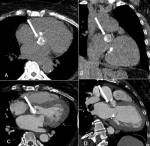

Chronologie et démarche diagnostique: au cours de son hospitalisation, la patiente a présenté des douleurs thoraciques ayant motivé la réalisation d'une échographie transthoracique qui a montré un rétrécissement aortique serré (SAo = 0,6 cm2), un anneau mitral calcifié, une insuffisance mitrale modérée et une insuffisance tricuspide sévère. Une coronarographie a été programmée dans le cadre du bilan préopératoire d'un remplacement valvulaire aortique et d'une plastie tricuspide, toutefois, le guide n'a pas pu franchir l'artère radiale probablement par la présence d'une infiltration athéromateuse sévère. Un coroscanner a été alors réalisé et a montré (Figure 1): i) Une calcification coronaire avec un score de calcique à 177 UH (unité Hounsfield); ii) Une calcification sévère mitrale et aortique avec des scores calciques mesurant respectivement 3992 et 3629; iii) Une formation hypodense de l'espace intervalvulaire précisément au niveau du trigone aortomitral, présentant une calcification fine périphérique, sans rehaussement après injection de produit de contraste, mesurant 25 x 10 mm dans le plan axial et 23 mm en coronal. Cette masse évoque une calcification caséeuse de l'anneau mitral.

Figure 1: A, B, C, D) aspect scanographique de la calcification caséeuse de la valve mitrale